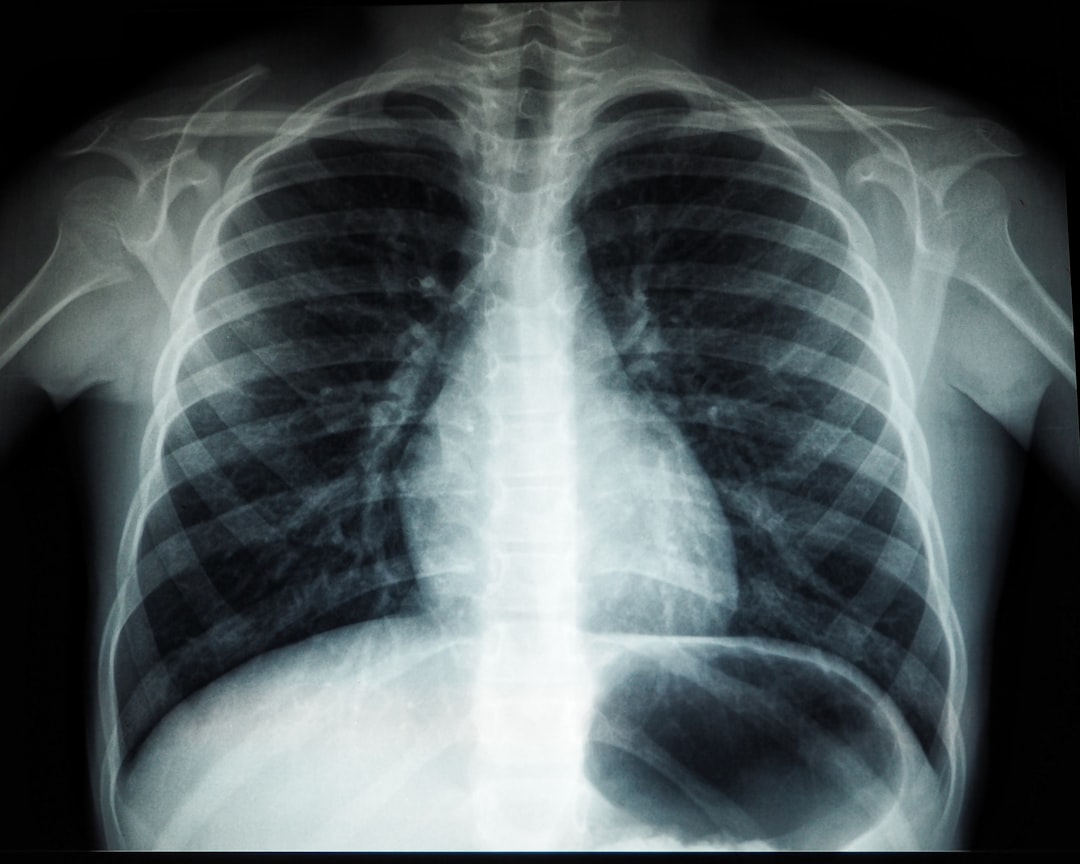

폐렴 입원기간: 개요

폐렴은 호흡기 질환으로, 폐의 염증이 주 원인이다. 감염에 의해 발생하며, 그 결과로 기침, 발열, 가슴 통증 등이 동반된다. 폐렴으로 인한 입원기간은 환자의 나이, 건강 상태, 치료 방법에 따라 다르게 나타난다. 일반적으로 성인의 폐렴 입원기간은 5일에서 10일 정도 소요되며, 상태가 더 심각할 경우 이보다 길어질 수 있다. 어린이와 노인의 경우, 폐렴 입원기간은 최장 14일까지도 연장될 수 있다.